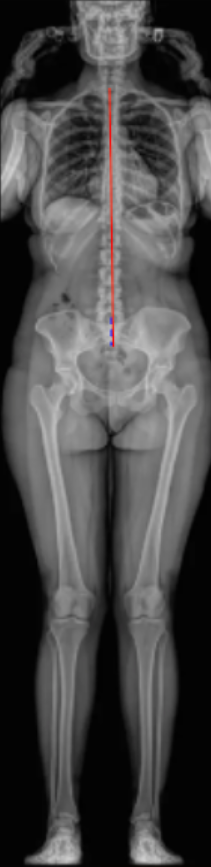

Trunk Shift quantifies the lateral displacement of the trunk relative to the pelvis in the coronal plane.

It is defined as the horizontal distance between the C7 plumb line (C7PL) and either the Central Sacral Vertical Line (CSVL) or the midpoint of the sacrum on a standing full-length spinal radiograph.

• A vertical plumb line extending upward from the midpoint of the sacrum (S1).

• Draw the C7 plumb line (C7PL):

• A vertical line dropped downward from the midpoint of the C7 vertebral body.

• Measure the horizontal distance (in millimeters) between the C7PL and the CSVL or the center of the sacrum.